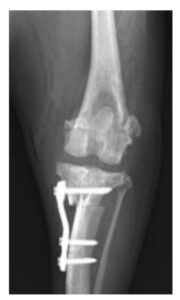

症例2. 膝蓋骨内方脱臼併発症例に対してTPLO-Mを実施した症例(12歳、チワワ、3 kg)

TPLO-M(TPLO-medialization)とは、膝蓋骨内方脱臼を伴う前十字靭帯断裂の犬において、

TPLOに脛骨粗面転移術を併用するのではなく、TPLOの脛骨近位骨片を内側に移動させることで、膝関節伸展機構のアライメントを整復する方法です。

| 治療前(側方像) | 治療後(側方像) | 治療前(前後像) | 治療後(前後像) |